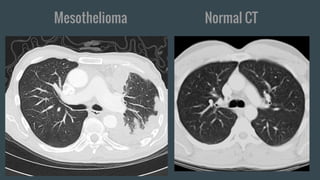

Mesothelioma Normal CT

Findings: Helpful in staging follow-up. Contrast-enhanced CT

used to assess tumor response to Chemotherapy. The calcified

pleural plaque indicates prior asbestosis exposure.

Impression: The lobulated pleural thickening in evident in the

right lung. Pleural effusion is minimal. Follow up pet scan to

confirm need for chemotherapy.